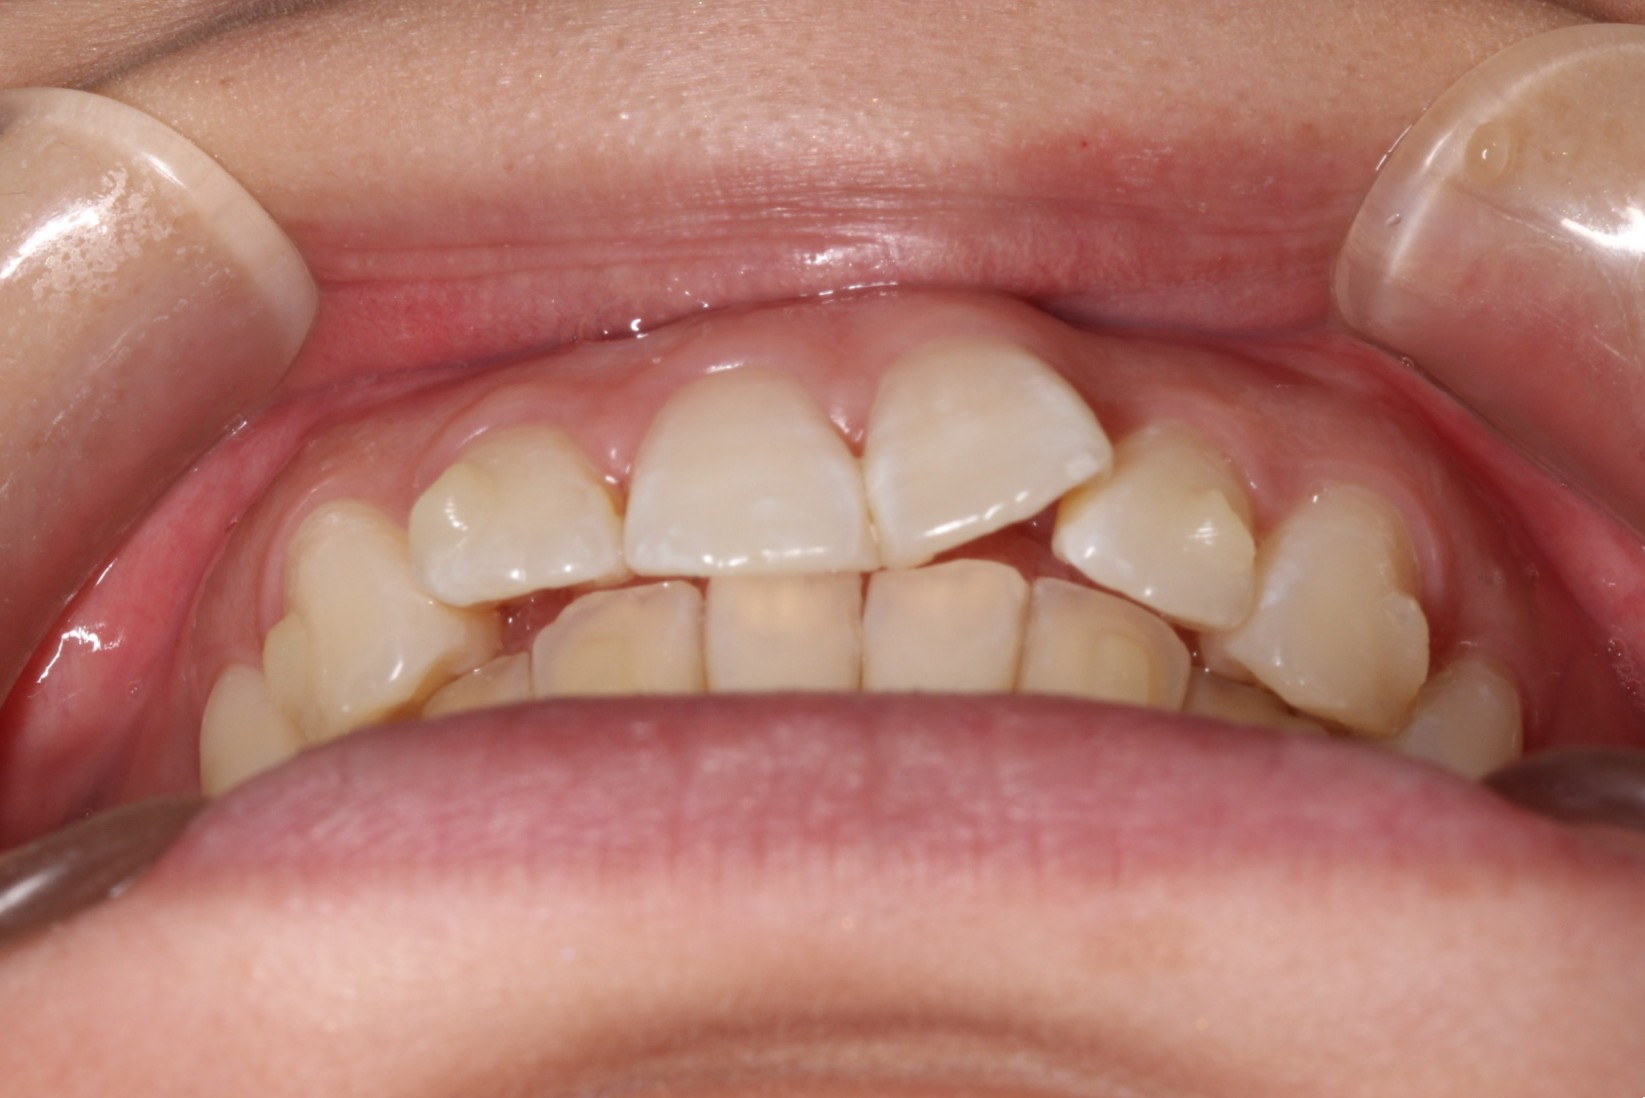

矯正術前:前歯部あおり

矯正術後:前歯部あおり